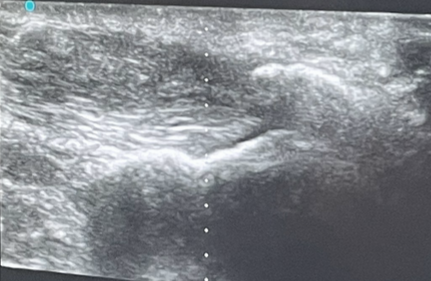

En corte longitudinal, se observa el tendón de Aquiles engrosado, hipoecogénico, con pérdida de la arquitectura fibrilar compatible con tendinosis, además de irregularidad focal compatible con secuela de rotura parcial. En corte transversal destaca calcificación intrasustancia y cambios degenerativos. Paratendón inferior y superior engrosados. Grasa de Hoffa con aumento de ecogenicidad sugerente de inflamación.

Se realiza infiltración ecoguiada con betametasona + levobupivacaína en paratendón inferior, superior y grasa de Hoffa. Se pauta reposo relativo, hielo local 48 h y reinicio de realización de ejercicios con carga de forma progresiva.